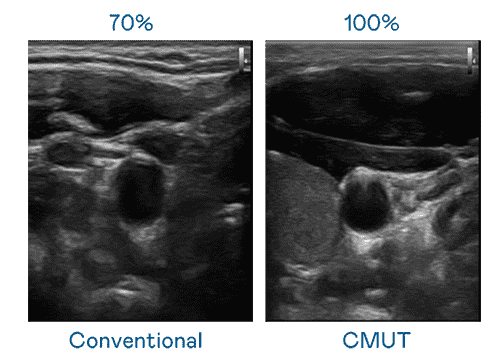

CMUT 技术是一种用电容式微机电元件来产生超音波讯号的技术。。。与传统 PZT 压电式技术相比,,CMUT 频宽增加 30%,,更宽频的超音波讯号让影像解析度大幅提升,,,,是实现高影像品质医疗超音波扫描、、促进精准医疗发展的关键技术。。。。

大频宽带来超清晰影像

超音波影像的解析度高低,,,,首先取决于探头能发出的讯号频宽。。人生就是博 CMUT 可提供高清晰的超音波讯号,,提供高频宽、、高灵敏度、、影像纹理细节更高的超音波影像,,,,协助医护人员缩短影像判读时间及利用精准的医疗影像进行诊断。。